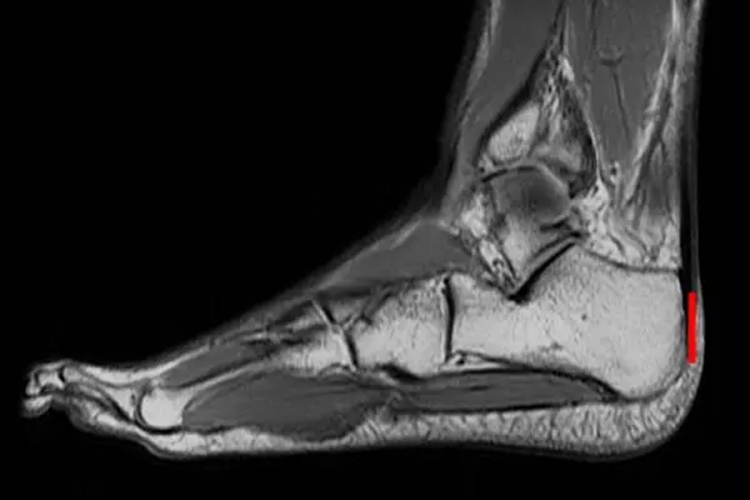

正常跟腱在核磁共振下可显示为质地均匀的低回声、纤维状结构。

跟腱是由小腿浅层肌群的腓肠肌和比目鱼肌的肌腱汇合而成,腓肠肌较比目鱼肌有较多的腱纤维参与跟腱的组成。正常跟腱在核磁共振下可显示质地均匀的低回声、纤维状结构,厚度一致,约5mm。跟腱近端呈扁平带状,越向远端走行越厚,并由轻微前凹后凸的形态变为椭圆形。